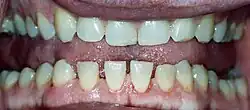

Lower jaw showing the classic spacing of teeth due to acromegaly.

Mandibular overgrowth leads to prognathism, maxillary widening, teeth spacing and malocclusion

• Pronounced lower jaw protrusion (prognathism) with attendant macroglossia (enlargement of the tongue) and teeth spacing